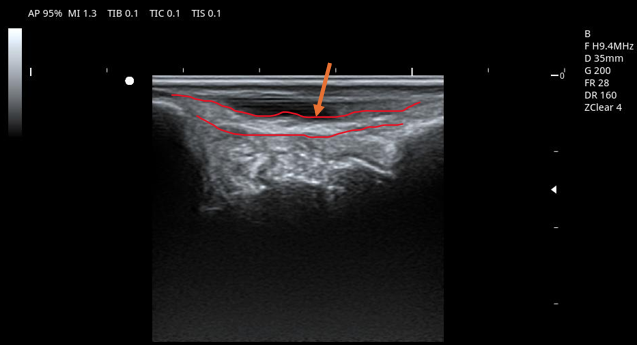

ついでなので超音波画像でも出しておきましょう。

三角靭帯(内側靭帯)の脛舟部の描出です。

矢印およびオレンジで囲われた部分です。

左端が内果、右端が舟状骨、真ん中の深い部分は距骨になります。

特に問題ないので綺麗に描出されていますが、前述のような三角靱帯損傷であれば、炎症を起こしていたりすると周囲に黒い部分が大きく映ったり、あるいは白い部分の連続性がなくなっていれば断裂の可能性があります。

処置としては先にも書いた通り固定になりますが、超音波で損傷度合いを確認することにより治癒までの期間を想定することが容易になります。また、プレイ復帰可能かどうかの判定も。